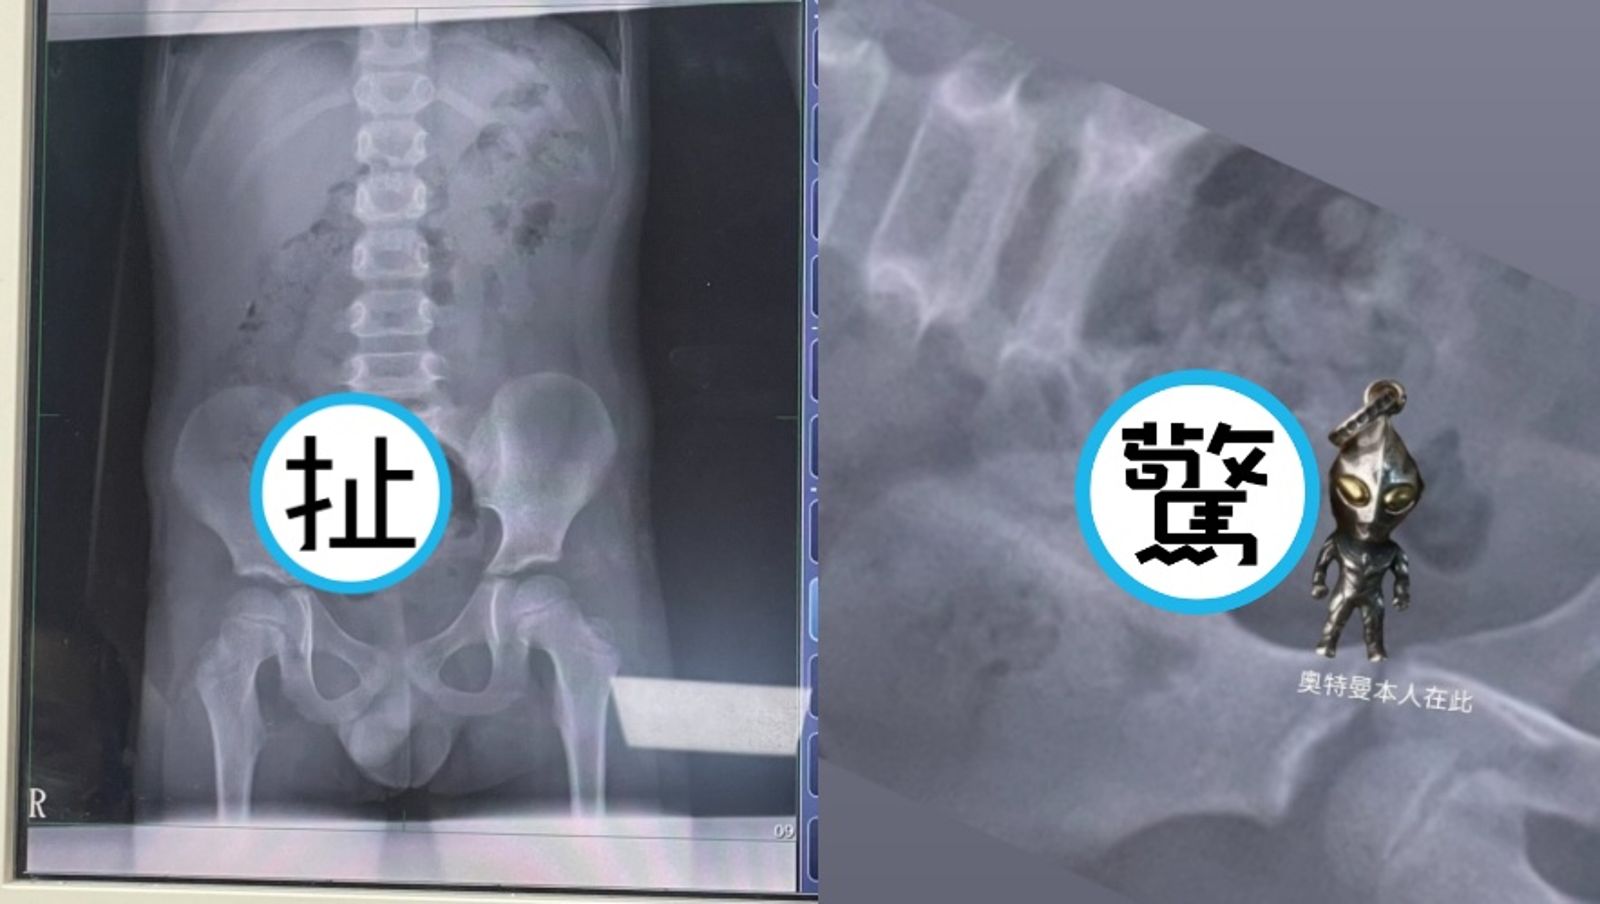

原PO更把吊飾與X光影像放在一起對照,並標註「奧特曼本人在此」,讓不少網友笑瘋,留言直呼:「這X光片可以帶回家裱框嗎?感覺很酷欸🤣」「大出來是不是變成奧德賽」「奧特曼已經快走到出口了,離開洞口會ㄎㄧㄤ一聲」「預產期是兩天後」「奧特曼:你相信光嗎」「如果是博愛醫院的話 我今天就在旁邊 聽到奧特曼也不小心笑出來….🤣」

家屬嚇壞立刻送孩子到羅東博愛醫院檢查,該院醫師謝錦桐指出,吊飾大小約2.8公分 ×1.4公分,目前已隨腸道蠕動到小腸,男童身體狀況良好,暫時不需動手術,回家後持續觀察,看是否能隨排便自然排出。